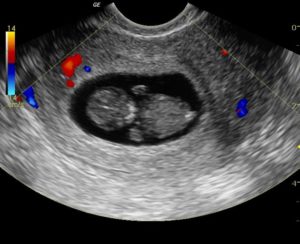

На основе перечисленных симптомов не констатируют патологию. Только после диагностических процедур можно установить точный диагноз. В процессе обследования женщина проходит гинекологический осмотр, ультразвуковое исследование и тестирование на уровень ХГЧ, а также сдает лабораторные анализы крови и мочи.

- диагностическое УЗИ (визуальное обследование матки, труб и яичников);